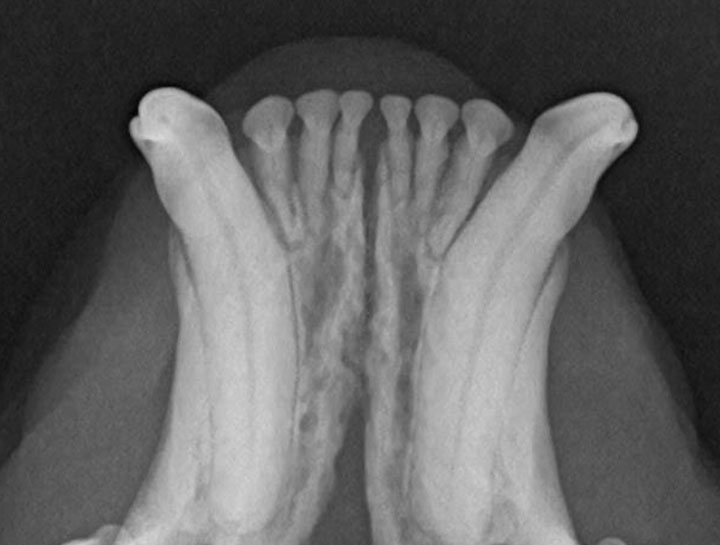

Digital Dental Radiology

Insight into underlying issues.